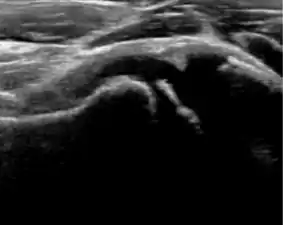

During childhood, ultrasound is a quick method to assess hip pain and quite often may be used to avoid use of irradiating techniques, such as radiography or CT. Ultrasound allows evaluation of joint effusion, synovial thickening and neovascularity, the bone/cartilage contour, and the femoral head-neck alignment. Although sonography is extremely sensitive in detecting increased synovial fluid, it is nonspecific and cannot be used with accuracy to determine the type of fluid. Transient synovitis of the hip, despite being the most frequent cause of pain in children between 3 and 10 years, remains a diagnosis of exclusion. It usually shows anechoic fluid, but echogenic fluid can also be found. The effusion is considered pathologic when it is measured at >2 mm in thickness. The differential diagnosis is wide, including osteomyelitis, septic arthritis, primary or metastatic lesions, LCPD, and SCFE. Discrimination from septic arthritis is challenging, often requiring joint aspiration. In septic arthritis, US is able to demonstrate a hip joint effusion, synovial thickening, and cartilage damage, although the appearances are nonspecific.[1]

A step between the head and the physis can be detected in children with SCFE, while abnormalities in the femoral head contour may suggest the presence of LCPD. In both cases, radiographs are mandatory to confirm diagnosis and severity (Figure 12).[1]

Figure 12:

-

Normal ultrasound appearance of the femoral head-neck junction. -

Joint effusion in transient synovitis of the hip. -

Flattening of the femoral head in a patient with Perthes disease. -

Step in the femoral head-neck junction in a patient with SCFE.